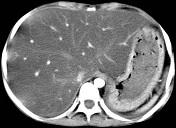

问题 男,57岁,肥胖、糖尿病、血脂升高,CT扫描如下图,请问诊断或描述错误的是哪一项 ( )

选项 A、密度均匀减低 B、血管影清唽可见 C、脂肪肝 D、肝脏增大 E、肝硬化

答案 E